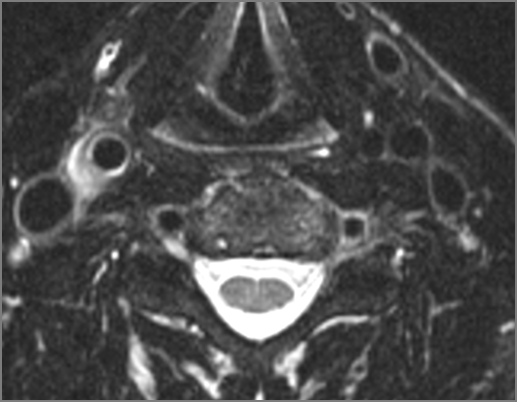

Hypopharynx, Larynx, Deep Neck and Entire Retropharyngeal Space

There is edema or abscess within in the hypopharynx, larynx or trachea. [Yes/No]

There is edema or abscess within the adjacent parapharyngeal and retropharyngeal spaces. [Yes/No]